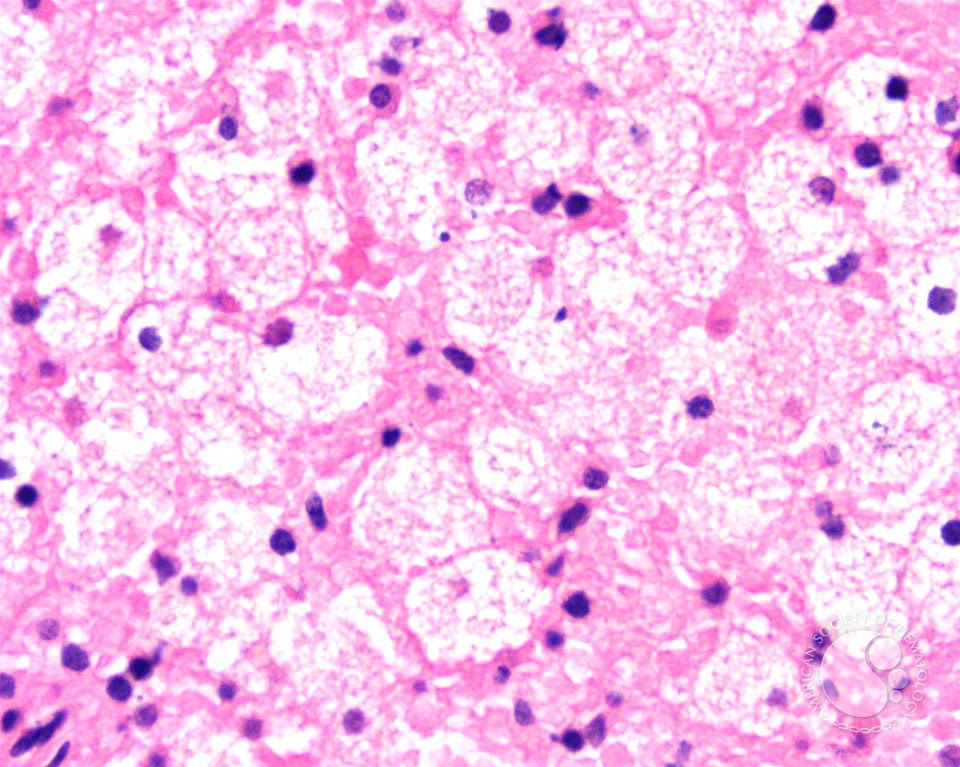

Splenic involvement in Niemann Pick disease - 4.

Splenic involvement in Niemann Pick disease - 4. from imagebank.hematology.org